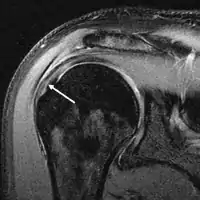

MRI

Magnetic resonance imaging (MRI) and ultrasound[42] are comparable in efficacy and helpful in diagnosis although both have a false positive rate of 15–20%.[43] MRI can reliably detect most full-thickness tears although very small pinpoint tears may be missed. In such situations, an MRI combined with an injection of contrast material, an MR-arthrogram, may help to confirm the diagnosis. It should be realized that a normal MRI cannot fully rule out a small tear (a false negative) while partial-thickness tears are not as reliably detected.[44] While MRI is sensitive in identifying tendon degeneration (tendinopathy), it may not reliably distinguish between a degenerative tendon and a partially torn tendon. Again, magnetic resonance arthrography can improve the differentiation.[44] An overall sensitivity of 91% (9% false negative rate) has been reported indicating that magnetic resonance arthrography is reliable in the detection of partial-thickness rotator cuff tears.[44] However, its routine use is not advised, since it involves entering the joint with a needle with potential risk of infection. Consequently, the test is reserved for cases in which the diagnosis remains unclear.

Diagnostic modalities, dependent on circumstances, include X-ray, MRI, MR arthrography, double-contrast arthrography, and ultrasound. Although MR arthrography is currently considered the gold standard, ultrasound may be most cost-effective.[31] Usually, a tear will be undetected by X-ray, although bone spurs, which can impinge upon the rotator cuff tendons, may be visible.[32] Such spurs suggest chronic severe rotator cuff disease. Double-contrast arthrography involves injecting contrast dye into the shoulder joint to detect leakage out of the injured rotator cuff[33] and its value is influenced by the experience of the operator. The most common diagnostic tool is magnetic resonance imaging (MRI), which can sometimes indicate the size of the tear, as well as its location within the tendon. Furthermore, MRI enables the detection or exclusion of complete rotator cuff tears with reasonable accuracy and is also suitable to diagnose other pathologies of the shoulder joint.[34]